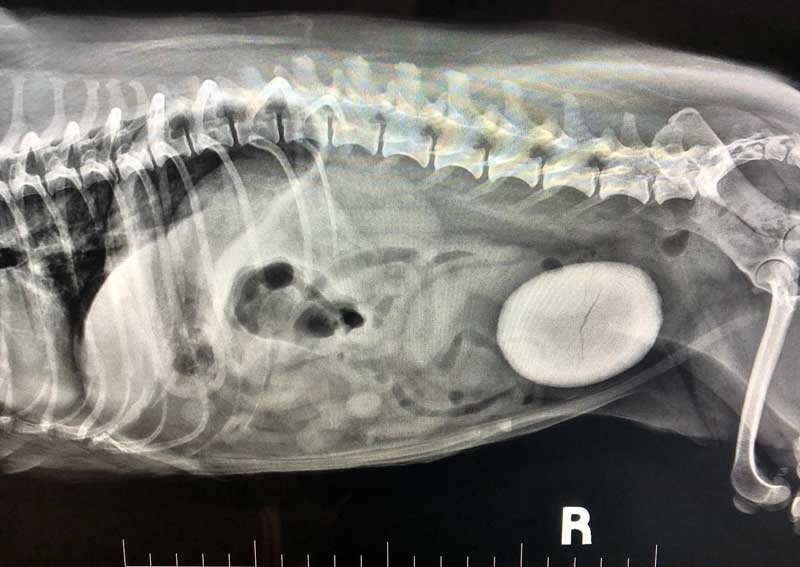

Is it a food coma or a belly emergency? Gastric Dilatation-Volvulus (GDV), or bloat, is when a pet’s stomach fills with gas, food, or fluid and twists on itself and is most common in deep chested dogs like Great Danes and German Shepherds but can happen in any breed. Learn what to do if your pet has eaten too much and when to call your veterinarian.